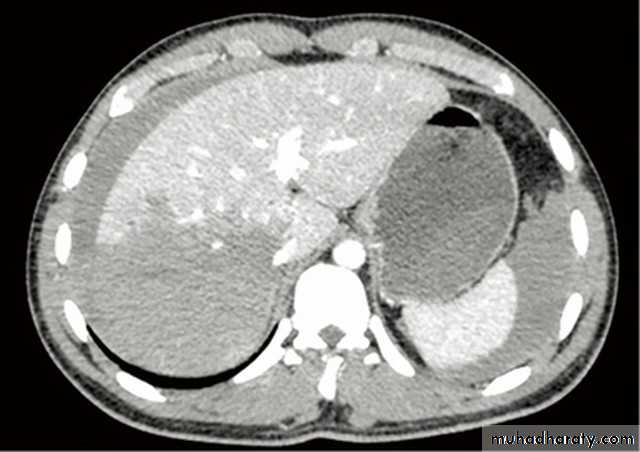

• CT of the abdomen is the imaging investigation of choice for detection of locally invasive disease, lymphadenopathy and distant metastases in patients with CRC.

• CT is unable to assess the depth of wall invasion or detect small metastases in non-enlarged lymph nodes. Therefore, CT is accurate for advanced disease though less so for earlier noninvasive disease.